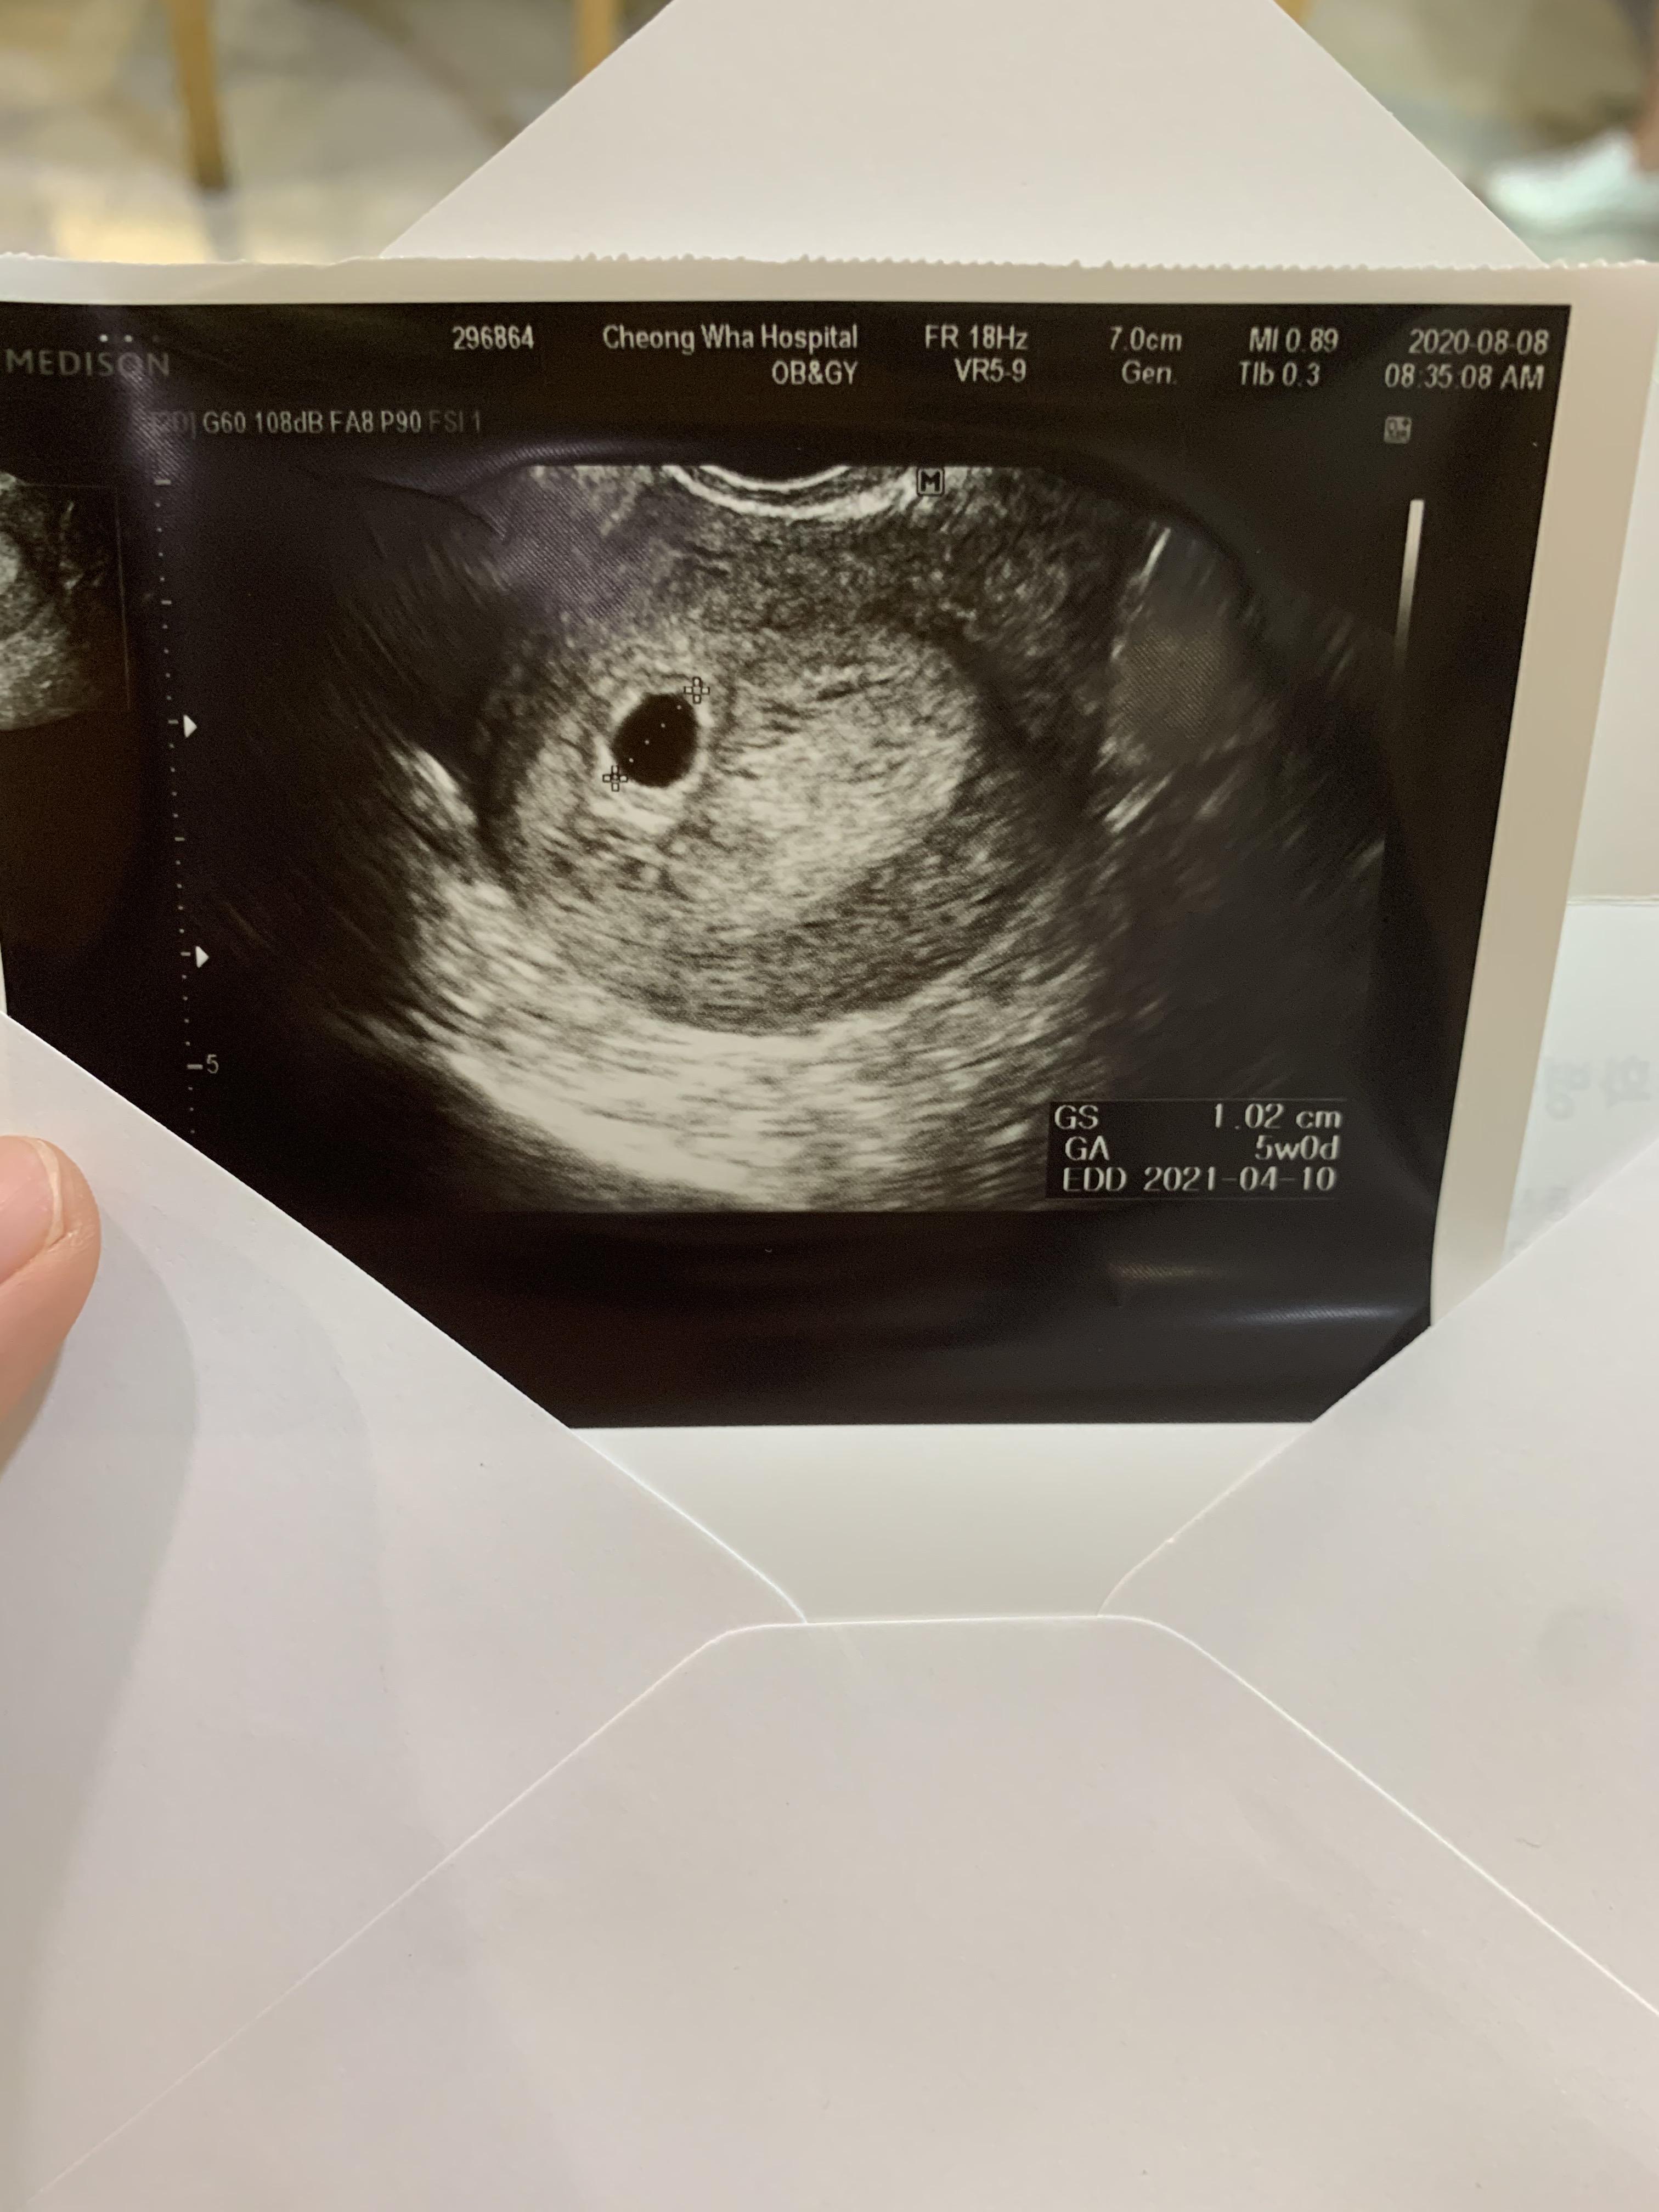

짜잔! 아기집이에요.

아기집 크기는 1센티이고,

아직 난황과 아이는 보이지 않는다고.

제가 계산한 5주차로 딱 맞게 진행되고 있다고 하시고,

털털한 여 선생님은 아마 3일정도 뒤에는 난황도 보일거라고

아직은 안보여도 괜찮은 주수라고 하시네요.